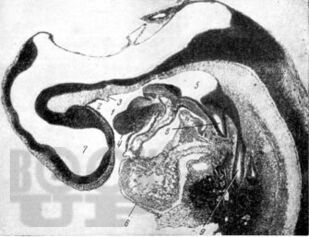

Учебное пособие предназначено для студентов стоматологического факультета медицинских вузов, включает основной теоретический материал гистологического строения органов ротовой полости в эмбриогенезе, необходимый для освоения частного раздела дисциплины - «Гистология и эмбриональное развитие органов ротовой полости». В каждой главе приведены основные морфологические характеристики эмбрионального этапа развития органов ротовой полости, механизм возможного нарушения эмбриогенеза, приводящий к врожденным аномалиям ЧЛО. Учебное пособие может быть использовано на практических занятиях, при подготовке к итоговой, промежуточной аттестации по гистологии.